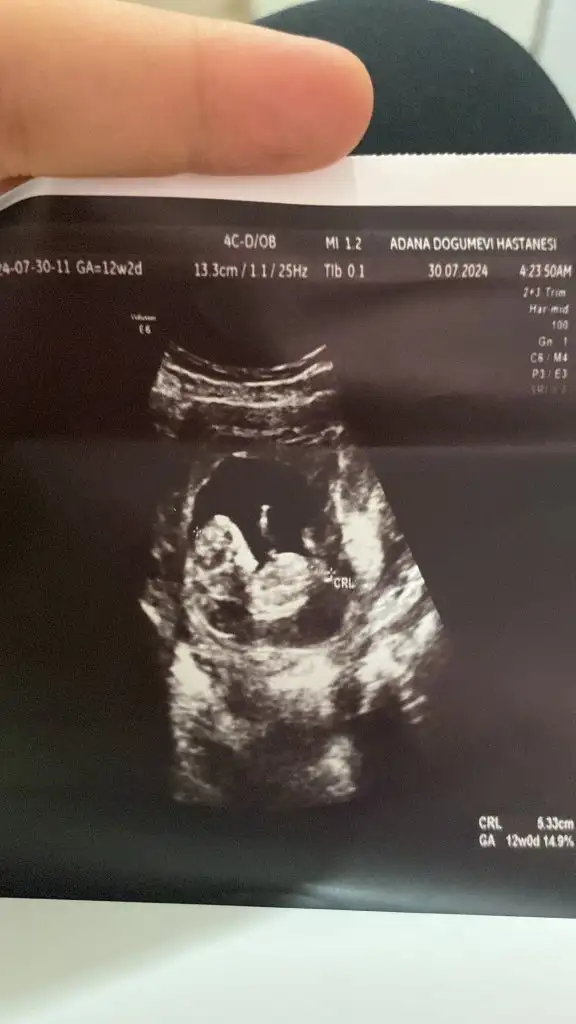

Bizim de bakar mısınız 10+1 bugün

• IMG_1404.webp

IMG_1404.webp

28,6 KB · Görüntüleme: 66

• IMG_1405.webp

IMG_1405.webp

41,6 KB · Görüntüleme: 69